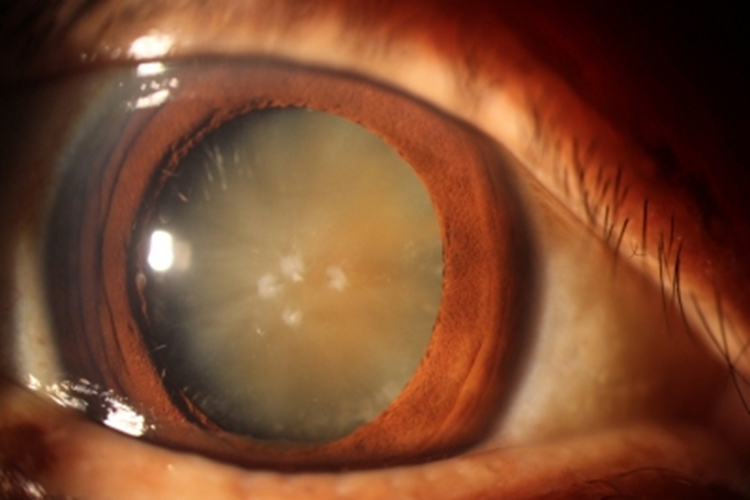

年龄相关性白内障随年龄增大,晶状体核密度逐渐增加,颜色变深,但对视力无明显影响。随病程进展患者的眼球颜色变深发黄,看起来像黄斑一样,边界清楚。